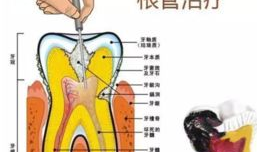

根管治疗视频,从视频学习根管治疗技巧与流程

最近是不是牙齿疼得你坐立不安,连笑容都变得苦涩了呢?别担心,今天就来给你揭秘一下那个听起来有点吓人的根管治疗,让你对这个过程有个...